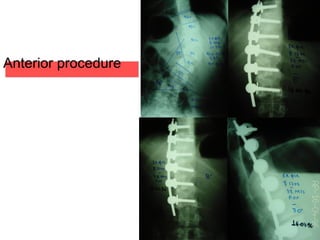

Thoracic stenosis and Myelopathy

•Anterior procedure

•Anterior decompression of the spinal cord

•Stabilization (cage and rods)